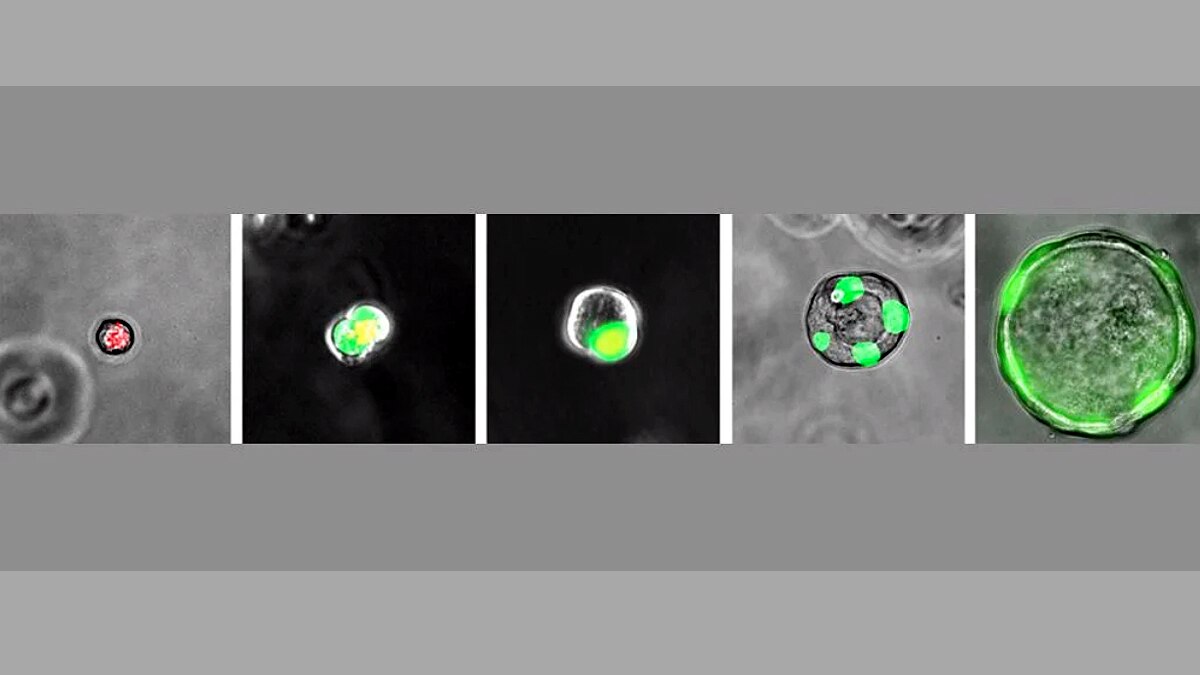

इस नए अंग यानी कोशिका को बेहर रोचक नाम दिया गया है. इसका नाम है रेस्पिरेटरी एयरवे सेक्रेटरी (Respiratory Airway Secretory - RAS). यह फेफड़ों के अंदर मौजूद नसों की शाखा ब्रॉन्किओल्स (Bronchioles) में मौजूद रहते हैं. इनका संबंध एल्वियोली (Alveoli) के साथ भी रहता है. ये वहीं अंग है जो खून के अंदर ऑक्सीजन और कार्बन डाइऑक्साइड का आदान-प्रदान करते हैं.  (फोटोः यूनिवर्सिटी ऑफ पेंसिलवेनिया)

RAS कोशिकाएं किसी स्टेम सेल्स (Stem Cells) की तरह होती हैं. इन्हें ब्लैंक कैनवास (Blank Canvas) कोशिकाएं कहते हैं, क्योंकि ये शरीर के अंदर किसी भी तरह के नए अंग या कोशिकाओं की पहचान करते हैं. ये क्षतिग्रस्त एल्वियोली को सुधारती हैं. नए एल्वियोली कोशिकाओं का निर्माण करती है. ताकि खून में गैसों का बहाव सही बना रहे.  (फोटोः गेटी)

प्रो. एडवर्ड मॉरिसे और उनकी टीम को फेरेट्स (Ferrets) के फेफड़ों में भी RAS कोशिकाएं मिली हैं, जो इंसानी कोशिकाओं से मिलती-जुलती हैं. इसके बात वैज्ञानिक इस नतीजे पर पहुंचे कि ज्यादातर स्तनधारी जीवों में चाहे वह छोटे हों या बड़े...उन सभी के फेफड़ो में RAS कोशिकाएं होती हैं.  (फोटोः गेटी)